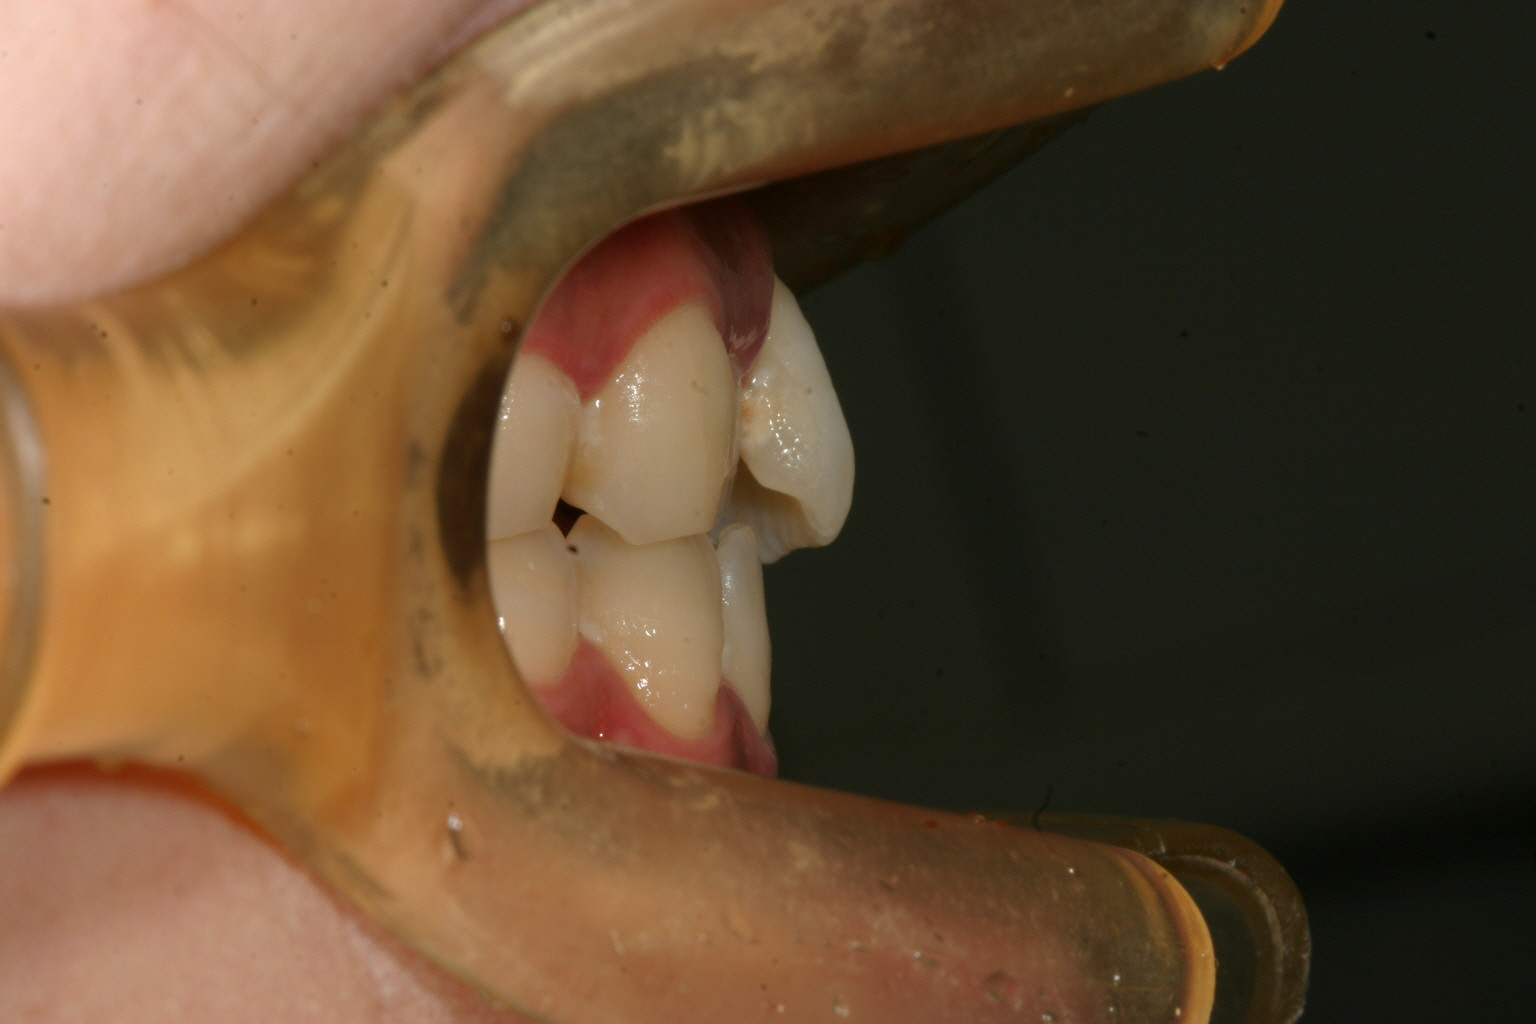

横から見た出っ歯感は前から見た感じより大した事無いですね!

綺麗に改善してますね~ 患者様がかなり頑張ってチューイ咬んで頑張ってくれました。